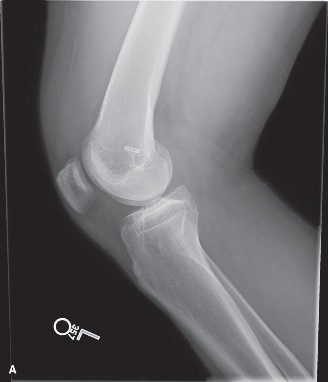

Standard weight-bearing radiographs, including anteroposterior (AP), lateral, Rosenberg (45-degree flexion posteroanterior), and Merchant views, are mandatory to assess bone stock, hardware placement, tunnel widening, and early degenerative changes.

The AP radiograph reveals metallic interference screws in both the femur and tibia. The tibial tunnel aperture appears significantly widened. Tunnel widening, or osteolysis, is a frequent complication in allograft reconstructions, driven by a combination of mechanical micromotion (the "bungee cord" and "windshield wiper" effects) and biological factors, including an exaggerated local cytokine response to the foreign allograft tissue and synovial fluid ingress into the bone tunnels.

The lateral radiograph is critical for evaluating tunnel position. In this patient, the femoral tunnel is noted to be placed anteriorly and vertically, high within the intercondylar notch. This vertical placement is a classic hallmark of the traditional transtibial drilling technique, which often sacrifices anatomic femoral footprint placement to accommodate the rigid trajectory of the tibial tunnel. A vertical graft effectively resists anterior tibial translation (Lachman) but fails utterly to resist internal rotation, leaving the patient with persistent rotatory instability (positive pivot shift).